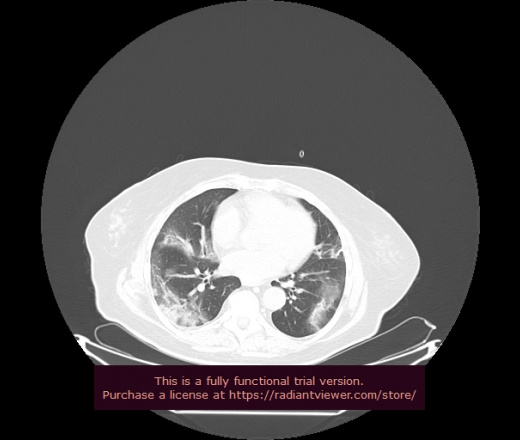

Уважаемые коллеги, если имеется интерес, сможете ли Вы спрогнозировать дальнейшее +-одинаковое течение процесса у 4 данных разных пациентов? Зацепиться где-то можно очень просто, где-то нельзя.